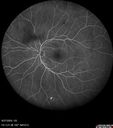

Central Retinal Vein Occlusion - Non-Ischemic - Excellent Outcome17 views57 year old man The right eye has had vision loss for about 3 weeks. He woke up with vision loss.

Medical Hx: HIV . Diabetes Mellitus (since 2014). Thyroid Disease.

Systemic Meds: gemboya. Metformin Hydrochloride. trulicity. losartan. vesepa. Synthroid .

VA OD: sc20/160 OS: sc20/20

TP: OD:14 OS:14

Treated with Avastin

VA 6 weeks later 20/32 – dry one shot.

Missed follow-up after second treatment and came 5 months later with good vision and no macular edemaAug 17, 2025